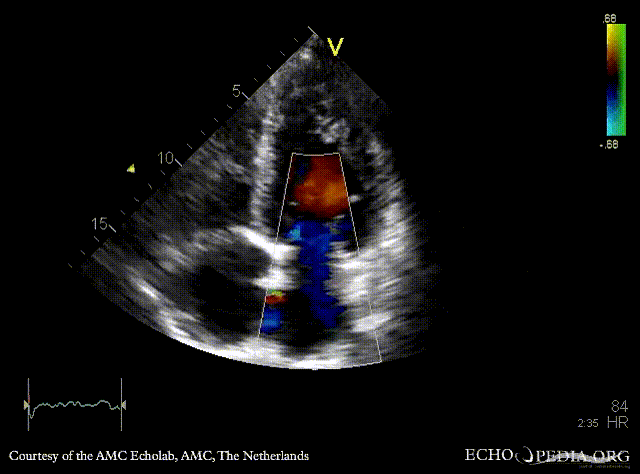

A4CH A4CH with Color Doppler: severe mitral valve regurgitation